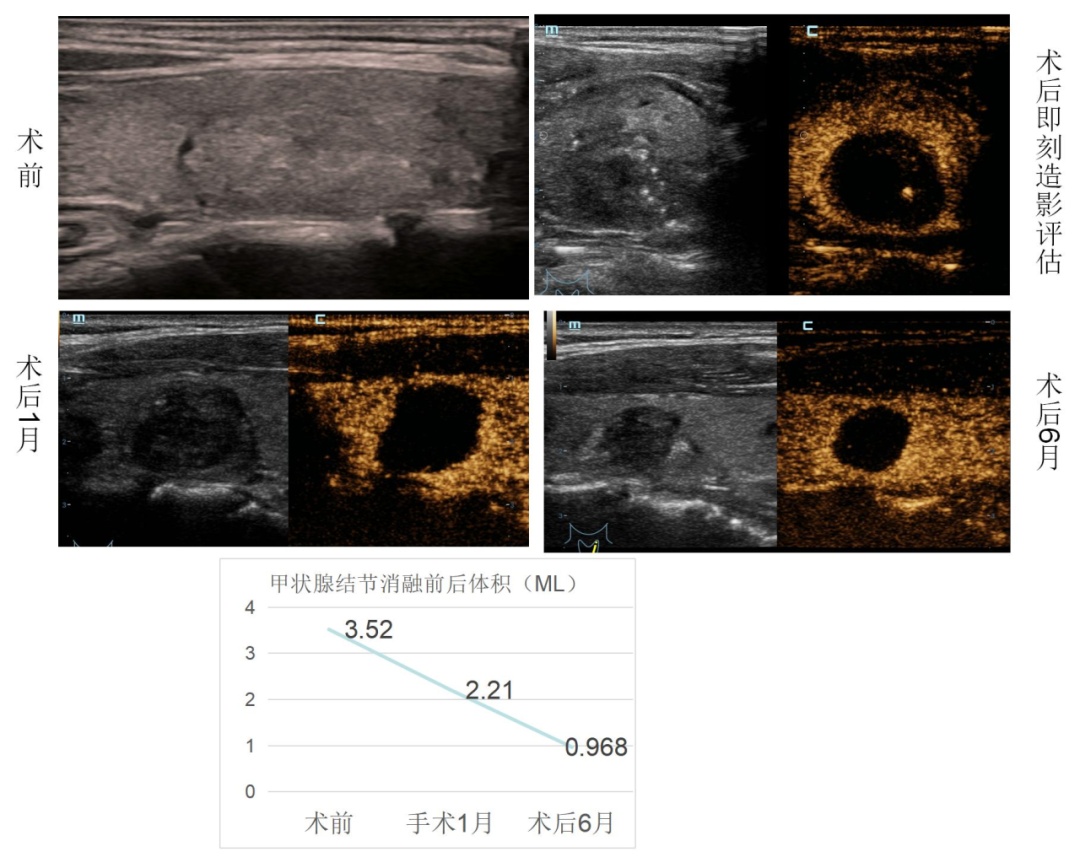

正规的甲状腺结节消融治疗,术前、术后即刻及术后不同时间均要进行超声造影检查评估消融范围。一般情况下,部分微小癌会在12个月左右自行吸收,良性结节在12个月左右会有不同程度的缩小。文献报道,良性结节治疗后随访3年,结节体积缩小率66.9% ~ 97.9%。但因为患者具有个体差异性,治疗效果会和人的免疫状态及结节具体情况有关。

甲状腺微小乳头状癌消融治疗后6个月,病灶完全吸收。

良性甲状腺结节,消融后6个月,结节体积减少为原先体积的1/3。